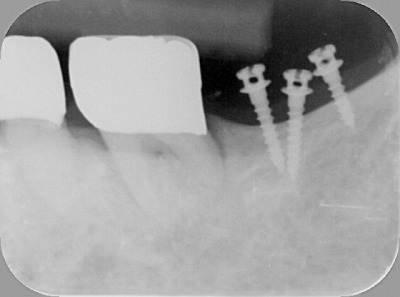

治療では、左下の奥歯に3本の矯正用インプラントを入れました。

レントゲンで見ると分かりますが、結構小さいインプラントです。

このインプラントを支えにして、奥歯を元の後側の位置まで引っ張りました。